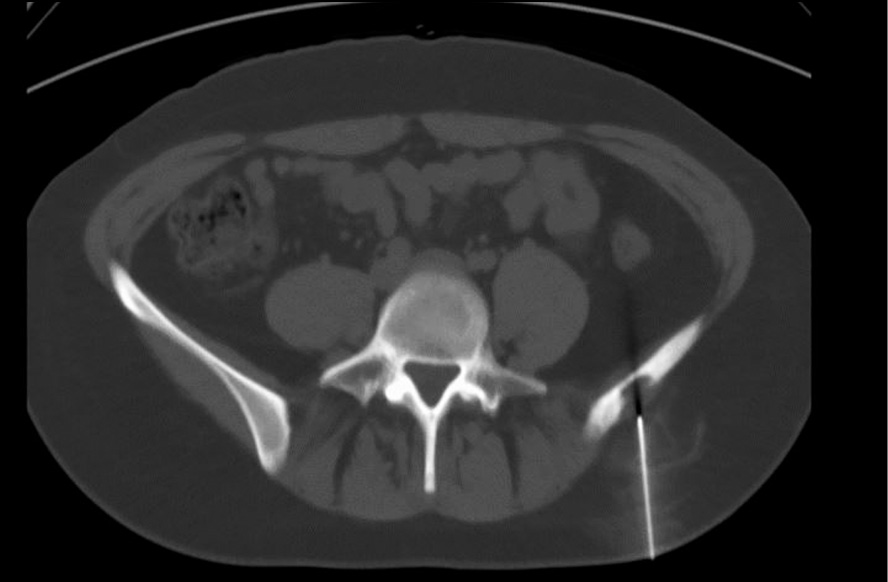

CT-guided 18G needle biopsy was performed from the wing formation of the left iliac bone (Fig. 3). The histological study (No. 2017-10802-01) concluded on the morphoimmunohistochemical presentation, which is most consistent with Langerhans cell histiocytosis (eosinophilic granuloma, histiocytosis X) (Fig. 4).

Fig. 3. The process of needle biopsy by computed tomography.